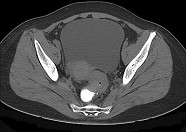

- 单项选择题男,67岁, 排便习惯改变,血便三个月入院, CT检查如图所示,下列说法错误的是  (    )

- A、直肠肠腔局限性增厚

- B、其表面欠光整,边界欠清晰

- C、可做直肠指检及活检以确定病变性质

- D、此为直肠息肉

- E、此为直肠癌